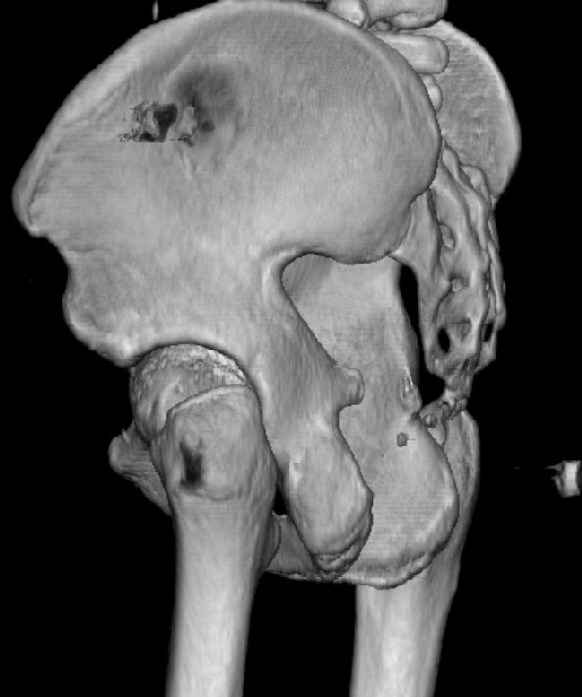

The last two images from the 3-D CT scan certainly makes the fracture look worse than the plan radiographs.

The joint is non-concentric as the head appears to be either "following the caudal segment", or the dome component is displaced from the tethered head... or so it seems... and he's young... so, many fracture surgeons would recommend reduction and fixation.

So we must decide preoperatively which part is the displaced segment?

It's difficult to know from these few selected images which component of the injury (was before and now) should be deemed the "soon to be mobile"

segment. It's my best guess that it is the caudal portion and there exists a healing fracture line somewhere thru the posterior column...one image

Some more images. Does it help to guess which part of the acetabulum is displaced?

Normal appearing SI joints and a healed posterior column limb... my bet's on caudal segment displacement.